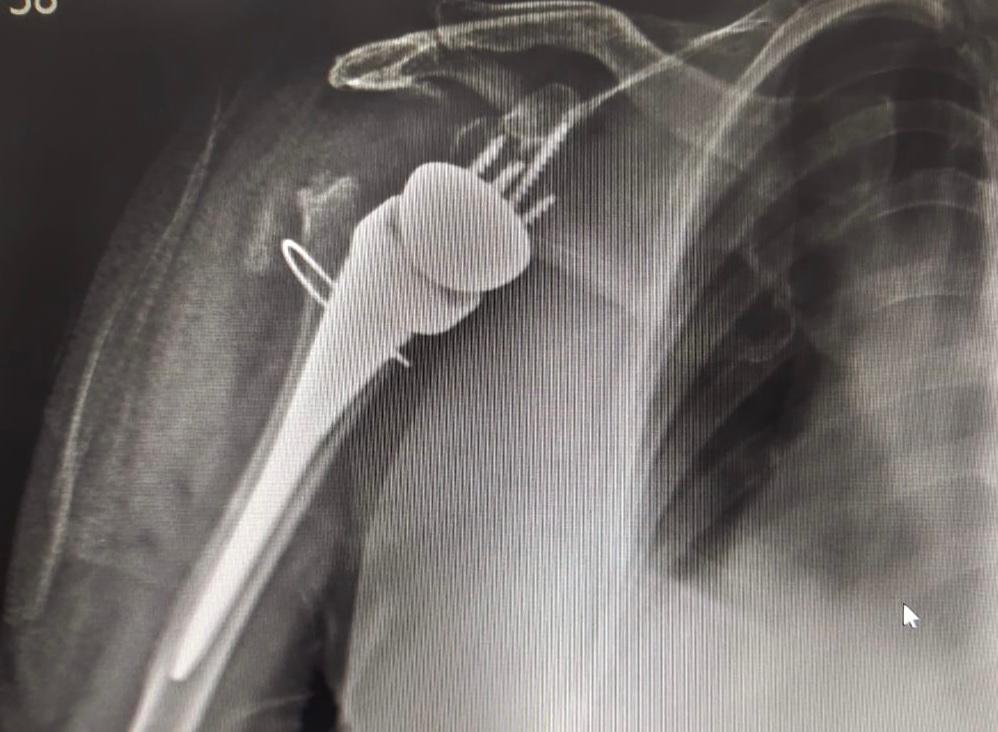

1) Total Shoulder Replacement

TSR (Total Shoulder Replacement) surgery performed on 80 yr old female with 4 part proxy humerus fracture following fall.

Reverse Shoulder Replacement